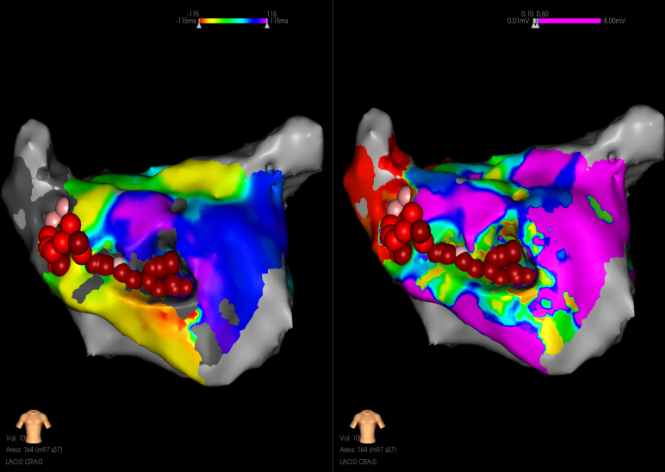

房扑再次发作:观察中再发房扑,周长为260-280,且CS顺序发生变化,遂重新进行激动标测。

激动从后壁沿着底部和左侧向前壁激动,形成顶部依赖的大折返。

顶部依赖折返激动图